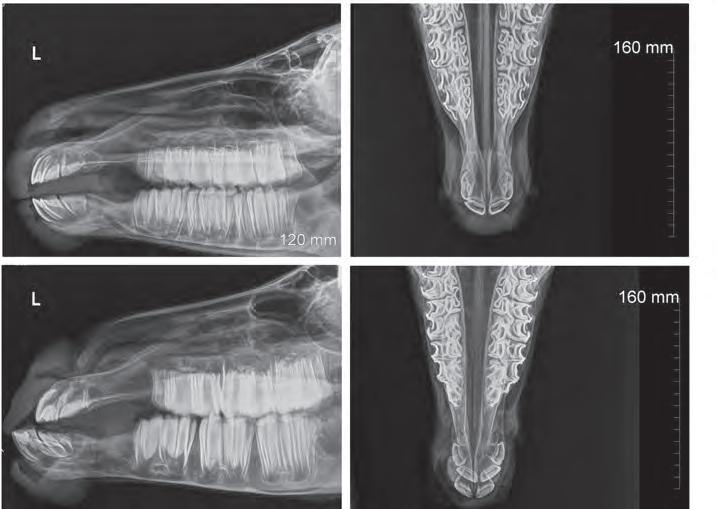

CHDS-affected foals can have symptoms including long gestation, low body temperature, enlarged thyroid glands, a “monkey mouth” (lower jaw extending

past the upper jaw), contracted limbs, ruptured tendons and poor small bone development in knees and hocks.

These X-ray images compare the mandibles (jaws) of a healthy foal (top) to a foal affected by CHDS (bottom). Both foals were less than one week old. Brooke Tonkin